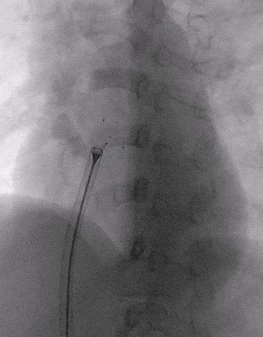

房间隔缺损介入封堵

根据术前测量结果,选择MemoSorb可降解ASD封堵器BDASD-I 14,配合14F可降解封堵器介入输送系统进行封堵。

建立输送轨道

导管导丝送入左上肺静脉

加硬导丝送入左上肺静脉,送入14F输送鞘

送入BDASD-I 14可降解ASD封堵器

展开左右盘面

左盘展开

右盘展开

锁定与牵拉试验

释放封堵器

释放后超声

超声下可见室水平和房水平都无残余分流